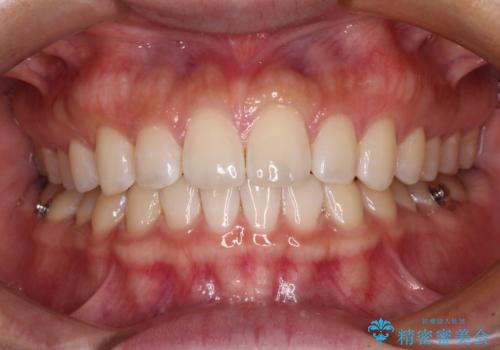

【モニター】前歯のすきっ歯をインビザラインで改善

- 上顎前歯の隙間と口元の突出感を気にして来院された患者様です。

高校生の時に行った矯正治療の後戻りであり、歯列不正は軽度であったので、インビザラインにて治療を行うこととしました。

すきっ歯はあっという間に後戻りを起こすので、可及的に後戻りを防止するために、上下前歯部を舌側からワイヤーで固定しています。

通常は下顎前歯のみに行っていますが、空隙歯列弓では上顎でも行っています。